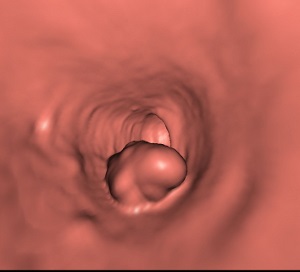

Aspect macroscopique du colonoscopie , sigmoidoscopie

et coloscopie virtuelle d'une adenome carcionoma du colon .

Aspect macroscopique de

coloscopie d'une adenocarcinoma du colon |

Coloscopie virtuelle :

Image d'une polyp a sessile du colon . Tech nique